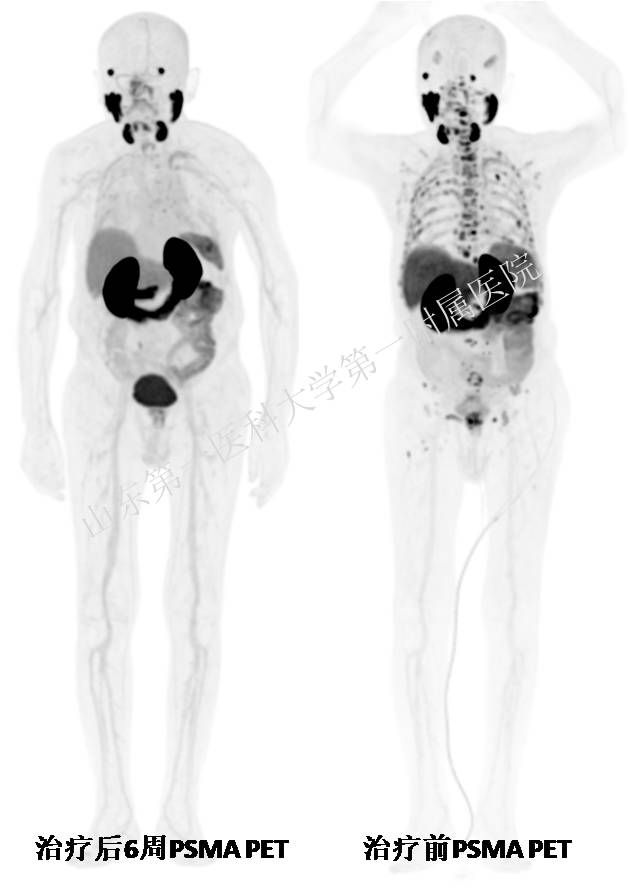

治疗6周后随访:家属称,患者精神、运动能力及食欲明显改善,体重较治疗前增加5公斤;肿瘤标志物PSA水平较治疗前显著降低,TPSA 0.079 μg/L,FPSA 0.009 μg/L;同时PSMA PET/CT显示患者全身肿瘤负荷显著降低、大部分肿瘤活性消失;“三重缓解”实现了晚期前列腺癌患者生活质量与临床疗效“双丰收”。

随访:PSMA PET可视化疗效,肿瘤显著缓解

治疗6周期间,医院核医学科及泌尿外科团队对患者全程密切随访,此次复查是治疗后首个关键疗效评估节点,核医学科主任程召平教授团队为其安排PSMA PET/CT显像,与治疗前对比显示:患者总体肿瘤负荷明显降低,综合疗效判定为“明显缓解”。